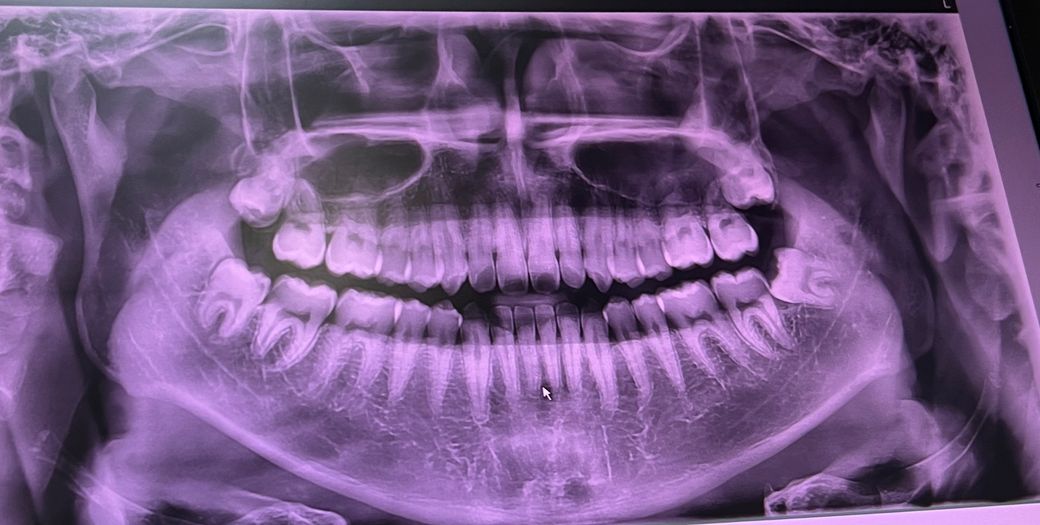

차가운물, 뜨거운물 먹을 때 시린게 아니라,

그냥 가만히 있어도 하악 전치가 시립니다.

그래서 치과를 갔더니 전치에는 충치가 없고 치경부마모증 얘기도 안하시더라구요. 그래서 걸론은 치석이 압박을 해서 그런걸 수도 있다고 해서 태어나서 처음 스케일링 받았습니다.

일단 감별해야할게 치아원인(치성) 통증인지부터입니다

치아가 원인이 되어 시린 경우는 지각과민, 치아마모, 교합문제 등이고요

그 외에는 잇몸퇴축, 신경성 통증등입니다